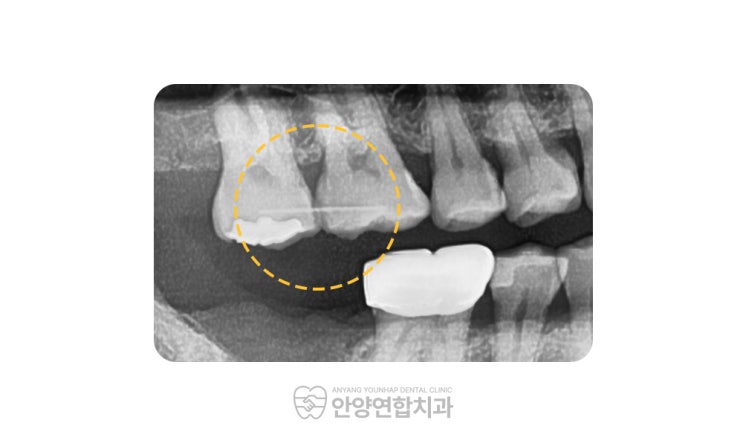

안양임플란트 치아정출예방까지 고려하는 치과에서

안양임플란트 치아정출예방까지 고려하는 치과에서 안녕하세요, 안양연합치과 대표원장 권영은입니다. 치아...